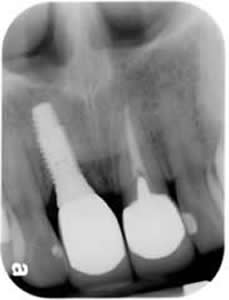

Front Single Tooth Implant:

Withou looking at the radiograph, can you tell which one is the implant tooth?